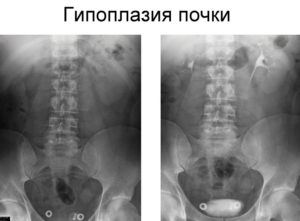

Для обнаружения несоответствия строения мочевыводящих путей производится экскреторная урография. Этот рентгеновский способ проверки предполагает вливание в кровь контрастного вещества – урографина.

Оно сразу после попадания в организм начинает удаляться почками, что позволяет ему окутывать лоханки, мочеточник, мочевой пузырь и мочеиспускательный канал. Рентгенснимки делаются трижды с интервалом в семь минут.

Для изучения физиологических особенностей малой почки применяют рентгеноконтрастную урографию. Специальное вещество вводят в вену, затем через каждые 10-15 мин. делают рентгеновские снимки, на которых видно прохождение контрастного вещества через орган. Благодаря снимкам определяют концентрационную и выделительную способность.